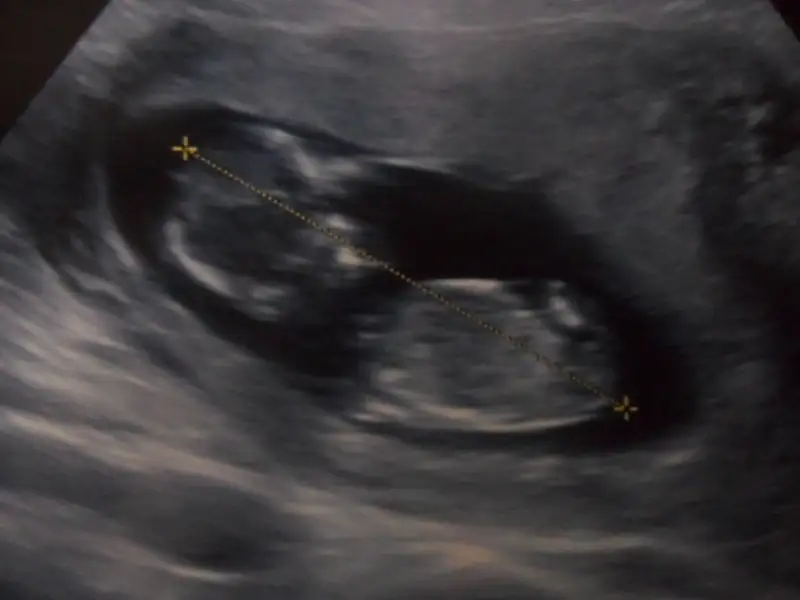

dr soylemeden siz gorun genital nub teorisi ( bebegin cinsiyeti)

yine de bir tahmin alayım orkdm çok olmuyorsam nub tam paralel degil sanki 30 luk açı var gibi bana göre ama testis falan da göremedim ben yine de bir bakarmısın buna? sf175

eger o kiyidaki nub ise ki pozisyon hic uygun degil kiz olabilir